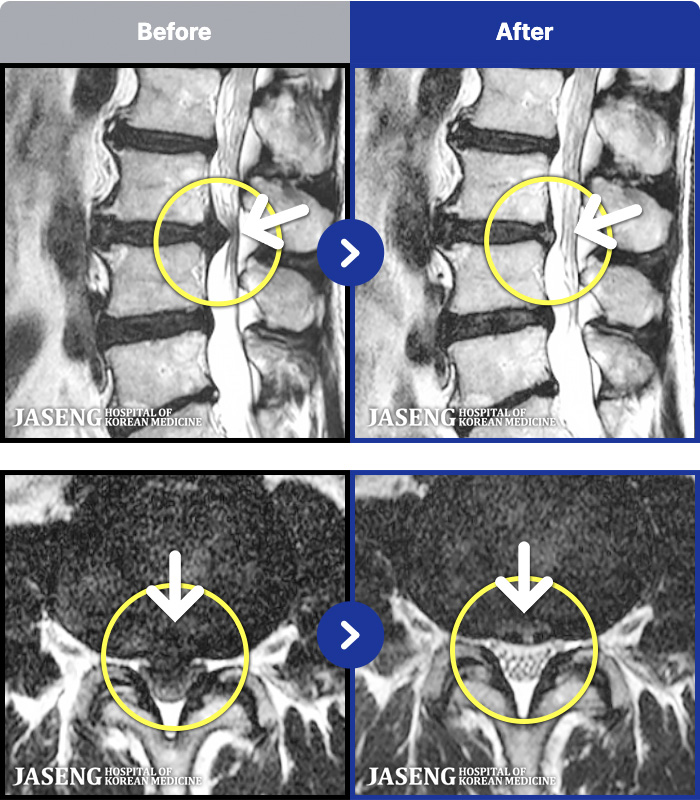

- MRI ġ

MRI ġ

1,304 MRI ũ ʸ Ȯϼ.